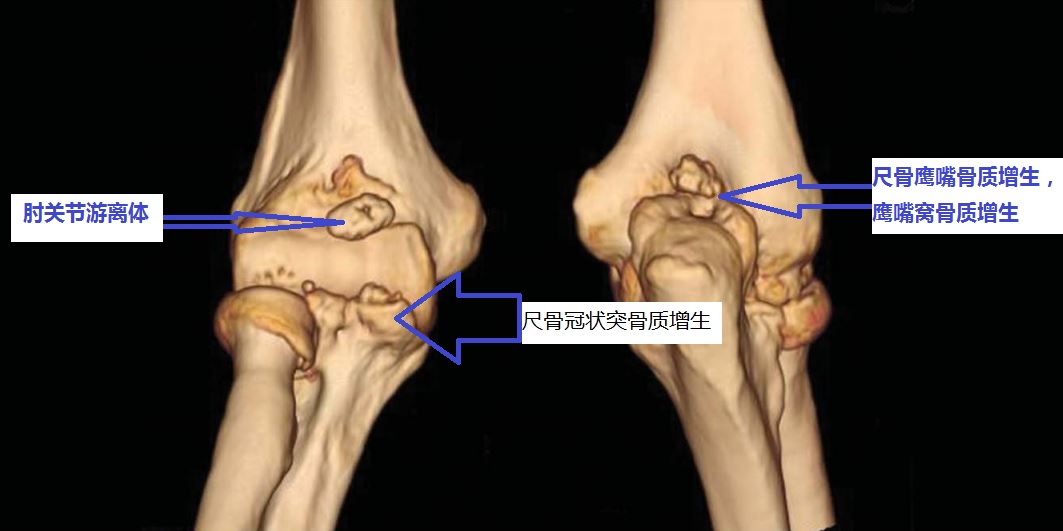

我们徐州1000万人口。其中有很多和您一样肘关节伸屈不行的患者。去年习*平近**主席两次到徐州视察进一步推进了我们徐州的快速发展。我们徐州发展过程中需要很多建筑工人。建筑工人师傅中有很多人来找我看肘关节问题。很多人都是由于肘关节骨性关节炎、肘关节游离体、肘关节骨质增生导致的肘关节僵硬。

伸不直往往是因为:1、尺骨鹰嘴骨质增生;2、肱骨远端后侧的尺骨鹰嘴窝骨质增生填塞;3、肘关节前侧的关节囊挛缩;4、肘关节内的游离体卡住了;等等。

屈不下来往往是因为:1、尺骨冠状突骨质增生;3、肱骨远端前面的尺骨冠状突窝骨质增生;4、肘关节后侧的关节囊挛缩;等等。